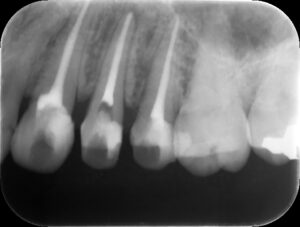

治療後レントゲン。適切な補綴(被せ物)により治療を終了。的確な診断および治療を行うことで、長年の悩みから解放された。我々は、無暗に患者さんの大切な人生の時間を奪ってはいけない。